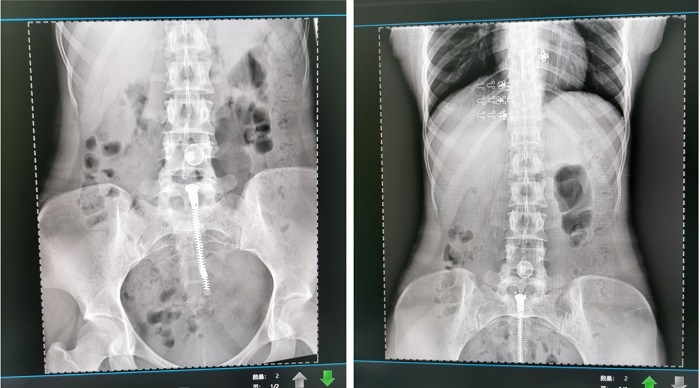

普利德懸吊DR采用高品質(zhì)平板探測器,滿足人體頭部、胸部、腹部、腰椎、四肢等部位的數(shù)字攝影檢查,成像速度快,圖像質(zhì)量高,可對肺野內(nèi)細微結(jié)構(gòu)顯示清晰,病變檢出率高,而且降低受檢者所接受的輻射劑量,這些優(yōu)勢在體檢篩查中對早期發(fā)現(xiàn)病變具有重要的意義。

在新生入學(xué)體檢中,除了優(yōu)質(zhì)的圖像質(zhì)量,普利德懸吊DR性能穩(wěn)定、操作便捷等優(yōu)勢,同樣得到了檢查醫(yī)生的高度認可,這些得益于設(shè)備卓越的影像鏈配置及智能化的運動設(shè)計。